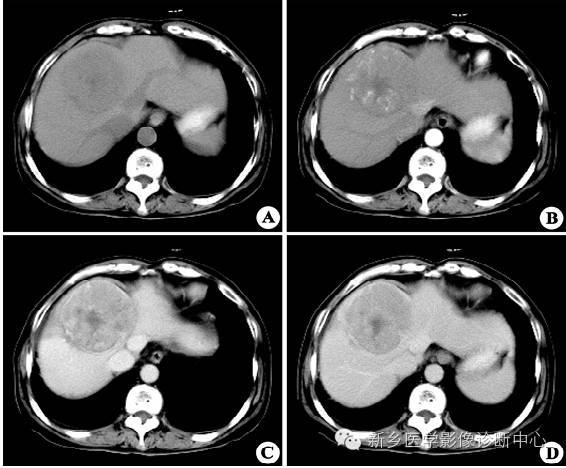

CT表现

1.平扫:肿瘤一般呈低密度,少数呈等密度。

2.动脉期:肝癌血供丰富,动脉期肿瘤明显强化,小肝癌常为均一增强浓染,大肝癌由于内部形成分隔,有不同的血管结构,而成不均匀增强效果,其差别较大。

3.门脉期:呈低密度或等密度。

4.延时扫描为低密度。